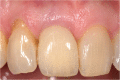

Introduction: Dental implants have become a standard treatment in the replacement of missing teeth. After tooth extraction and implant placement, resorption of buccal bundle bone can pose a significant complication with often very negative cosmetic impacts. Studies have shown that if the dental root remains in the alveolar process, bundle bone resorption is very minimal. However, to date, the deliberate retention of roots to preserve bone has not been routinely used in dental implantology.

Conclusion: Whilst the socket-shield technique potentially offers promising outcomes, reducing the need for invasive bone grafts around implants in the aesthetic zone, clinical data to support this is very limited. The limited data available is compromised by a lack of well-designed prospective randomised controlled studies. The existing case reports are of very limited scientific value. Retrospective studies exist in limited numbers but are of inconsistent design. At this stage, it is unclear whether the socket-shield technique will provide a stable long-time outcome.